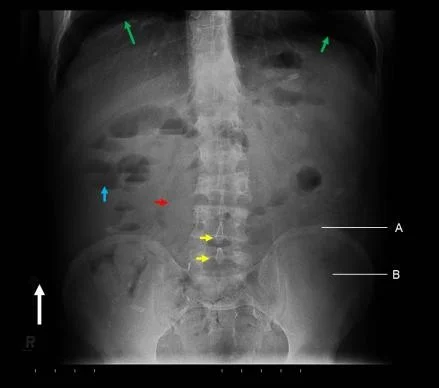

Use Anatomical Description

Annotated Features:

- Diaphysis

- Metaphysis

- Epiphysis

- Growth plate (appears twice)

- Patella or Sesamoid bone (bone inside a tendon)

- Apophysis (normal)

Additional Notes:

- If there was calcification in a specific area, itâs called Fabella.